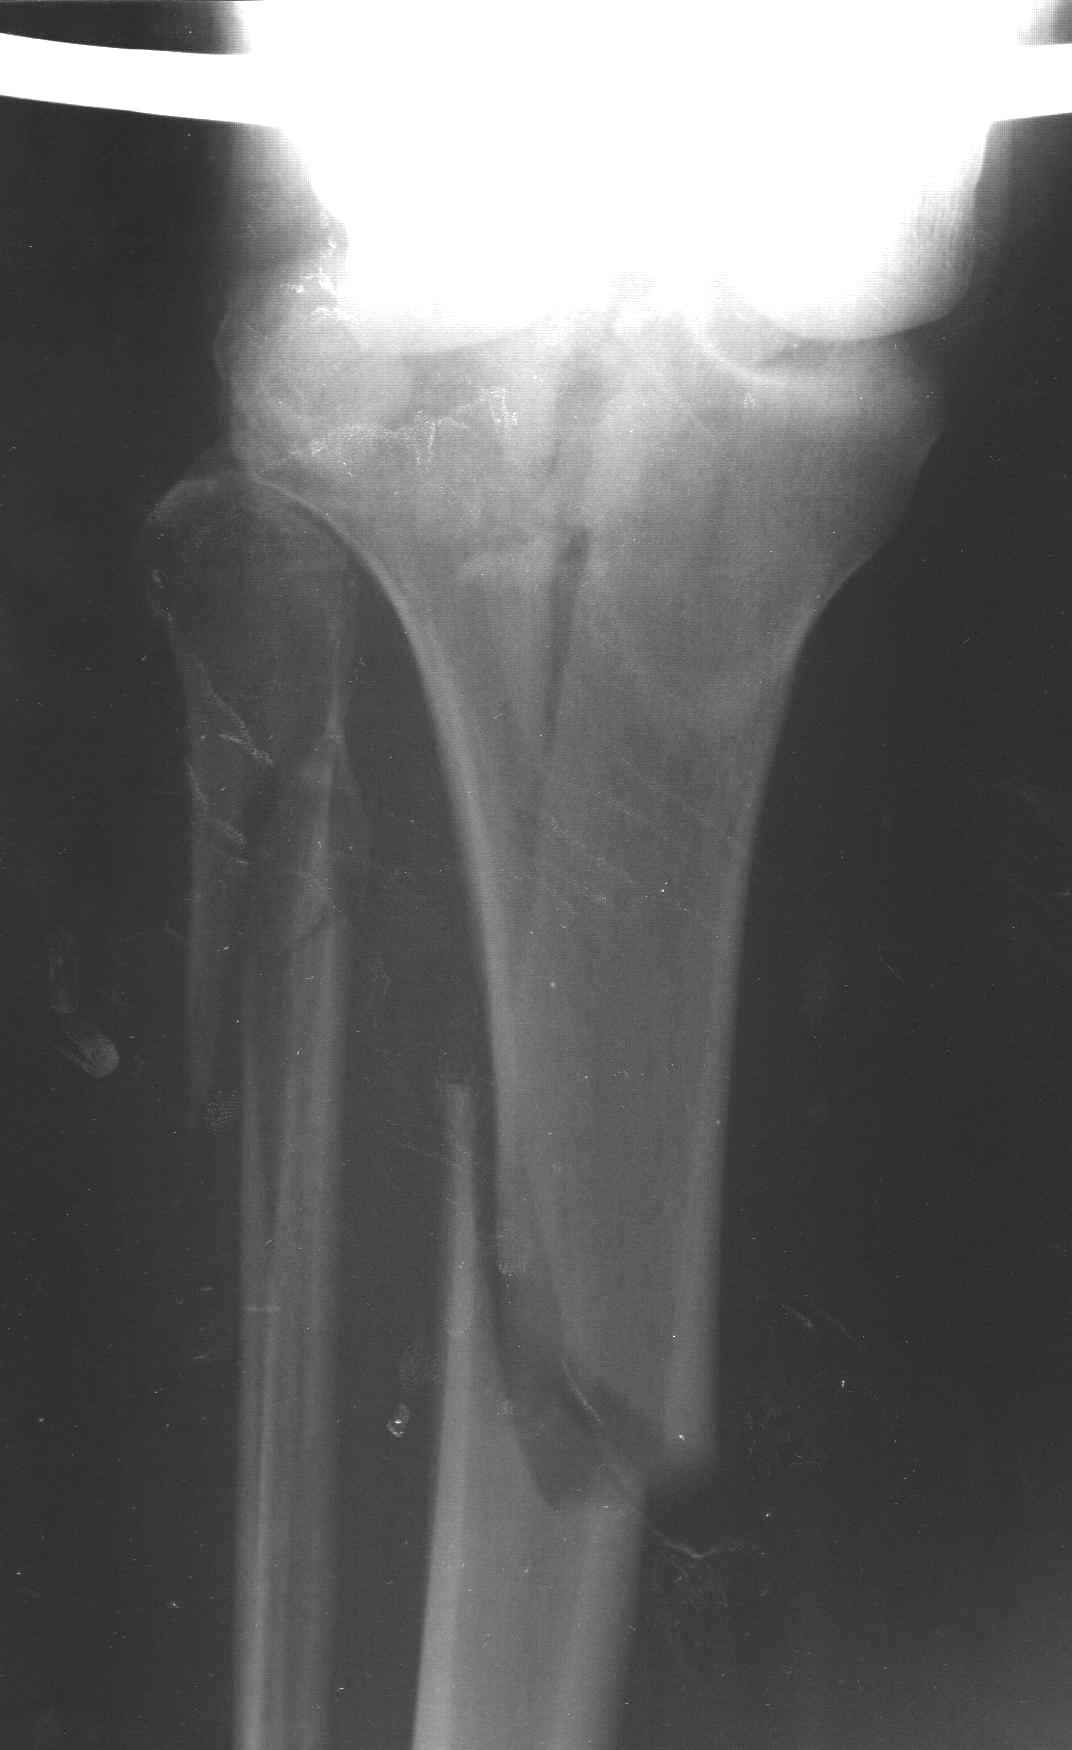

Пациенту сделали КТ - ухитрились сделать на шине Белера (не давал положить прямую ногу) - срезали передний отдел. Планируется на пятницу (24.12) на операцию - синтез длинной мыщелковой LCP-пластиной Synthes :). Отек ближе к слову умеренный (окружность голени +4 см по сравнению со здоровой). КТ и снимок на вытяжении прилагаются.